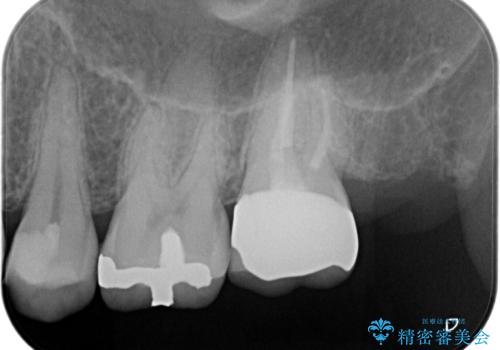

治療にて歯髄は保存できないと判断したため、根管治療を行いセラミッククラウンにて修復しております。

自発痛の既往がある場合は、抜髄の適応となることが多いです。